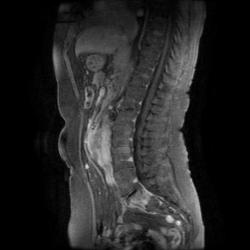

Женщина 47 лет, в течении долгого времени страдала от головных болей. В последние несколько месяцев - прогрессирующая потеря зрения (на оба глаза).

T2 ВИ Sagittal

Случай "учебный", и сложностей не должен представлять.

Presented images are corresponded for cerebral (right temporal-occipital region) neoplasia; high grade glioma is most suggested.

Глиальная опухоль.